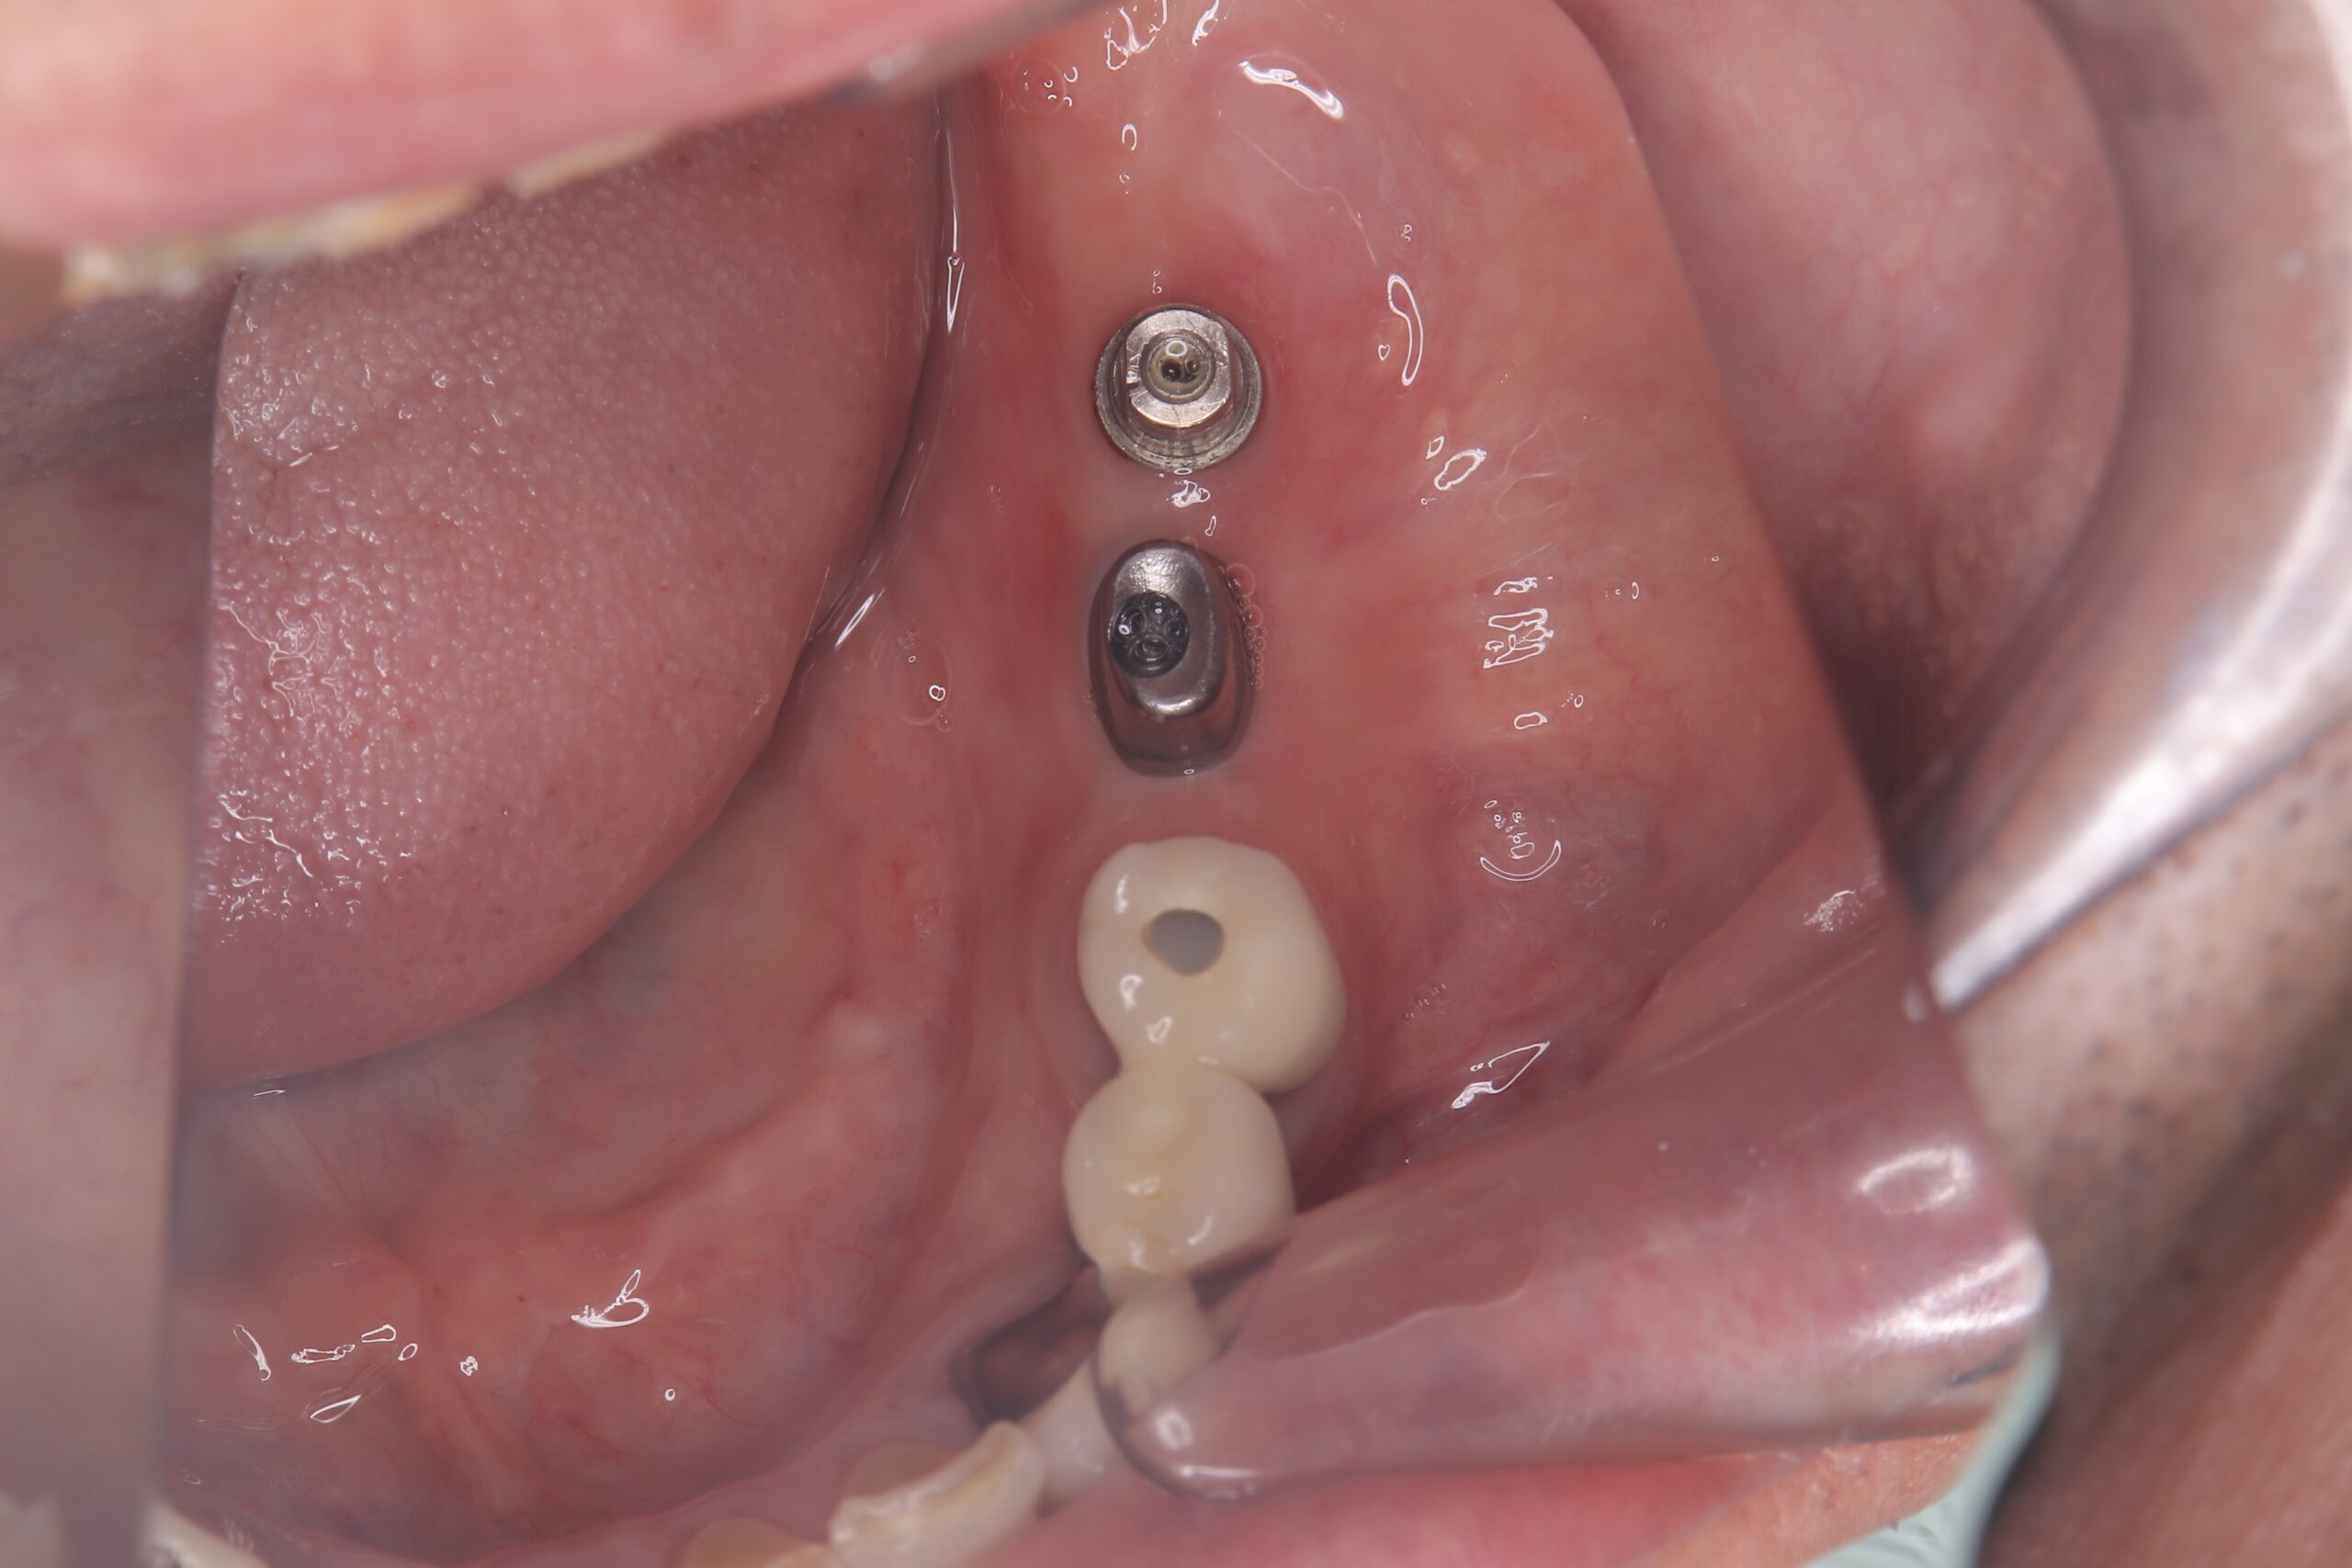

インプラント体にアバットメント(土台)装着

-